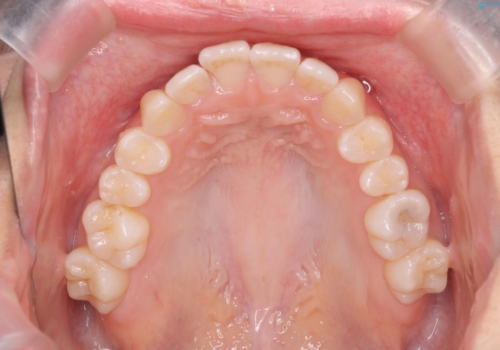

歯を抜かないで出っ歯を治したい

- 前歯が出ていることを主訴に来院。

歯を抜かずにマウスピース矯正をご希望でした。

歯と歯の間をわずかに削り、歯並びを少し横に拡大して並べました。

奥にすき間がなかったため後ろには下げていません。

沢山ひっこめるには4本抜歯でワイヤーの選択肢もありましたが、抜かないでできる範囲をご希望されました。

とがった形の歯列を整えるだけでもだいぶ印象は変わると思います。

今回歯列を広げた結果、上顎犬歯の歯肉は多少退縮しています。